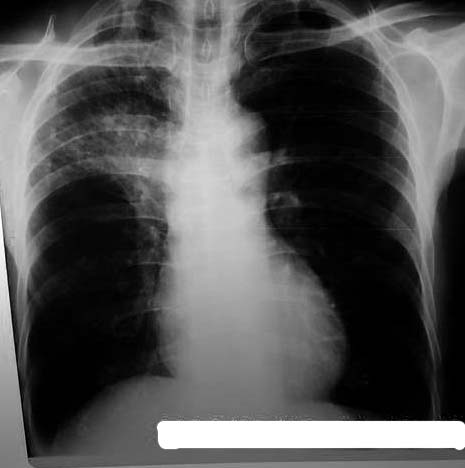

以下是引用jiangjing在2006-7-20 19:22:00的发言:[br]右侧肺门见有软组织肿块,边缘不规则,不光整,其周围肺内见炎性片状影,胸片示水平裂呈弧形上移,右上叶支气管狭窄,考虑右肺中央型肺癌伴阻塞性肺炎部分肺不张。